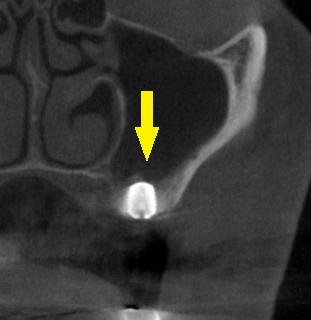

下の写真、下段が手術後のCTです。

第一大臼歯部には直径6.0mm、長さ7mm、第二大臼歯部には直径6.0mm、長さ8.5mmのインプラントを埋入しました。